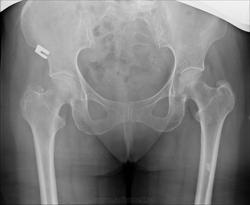

Помогите, пожалуйста, разобраться: что в в/з бедренной кости слева?

Это не ваш артефакт?

Судя по http://www.radiologyassistant.nl/en/p4bc9a97980036/sclerotic-bone-tumors-and-tumor-like-lesions.html#i4bc9acec07911 похоже на оссифицирующуюся фиброму.

похоже на оссифицирующуюся фиброму.

Эностоз.

И я выскажусь за эностоз. И ещё какой-нибудь остеоме уделю внимание - добавлю в диф. ряд. Для рентгенолога (с учётом МРТ) будет ведь интересно разграничить предложенные варианты. Вы потом скажите, что было в результате на дообследовании у Вас.

При диагностике образований костей очень важен возраст. Сколько лет пациентке?

А что за тень в проекции медиальных отделов левой вертлужной впадины, наслаивающаяся на головку? Или это нормальное строение кости?

Возможно так выглядит субхондральный склероз вертлужной впадины вне ее крыши.